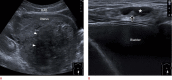

Inguinal hernia is the most prevalent type of abdominal wall hernia. Indirect inguinal hernia is twice as common as direct inguinal hernia. Computed tomography and magnetic resonance imaging can be used to evaluate inguinal hernia, but these modalities are greatly limited by their cost and availability. Ultrasonography has emerged as the most convenient imaging tool for diagnosing inguinal hernia due to its advantages, such as portability and absence of radiation. The present pictorial review presents an overview on the use of ultrasonography in the evaluation of inguinal hernia with a particular emphasis on the regional anatomy, relevant scanning tips, identification of subtypes, postoperative follow-up, and diagnosis of pathologies mimicking inguinal hernia.